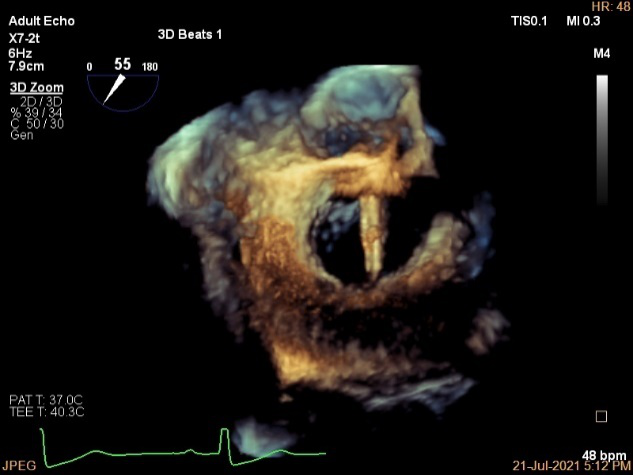

3D MV View

3D-color MV view:血流主要来源于2区近3区

Qlab软件勾画估测瓣口面积约:6.16cm²

3D视图打开夹子

3D视图下调Rotate,定位2区

3D视图下观察二尖瓣双孔形态